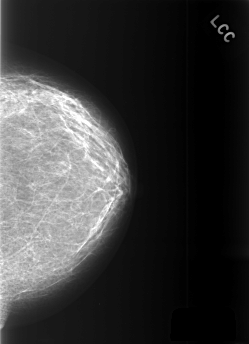

C_0369_1.LEFT_CC

LEFT_CC LINES 5504 PIXELS_PER_LINE 3984 BITS_PER_PIXEL 12 RESOLUTION 50 NON_OVERLAY